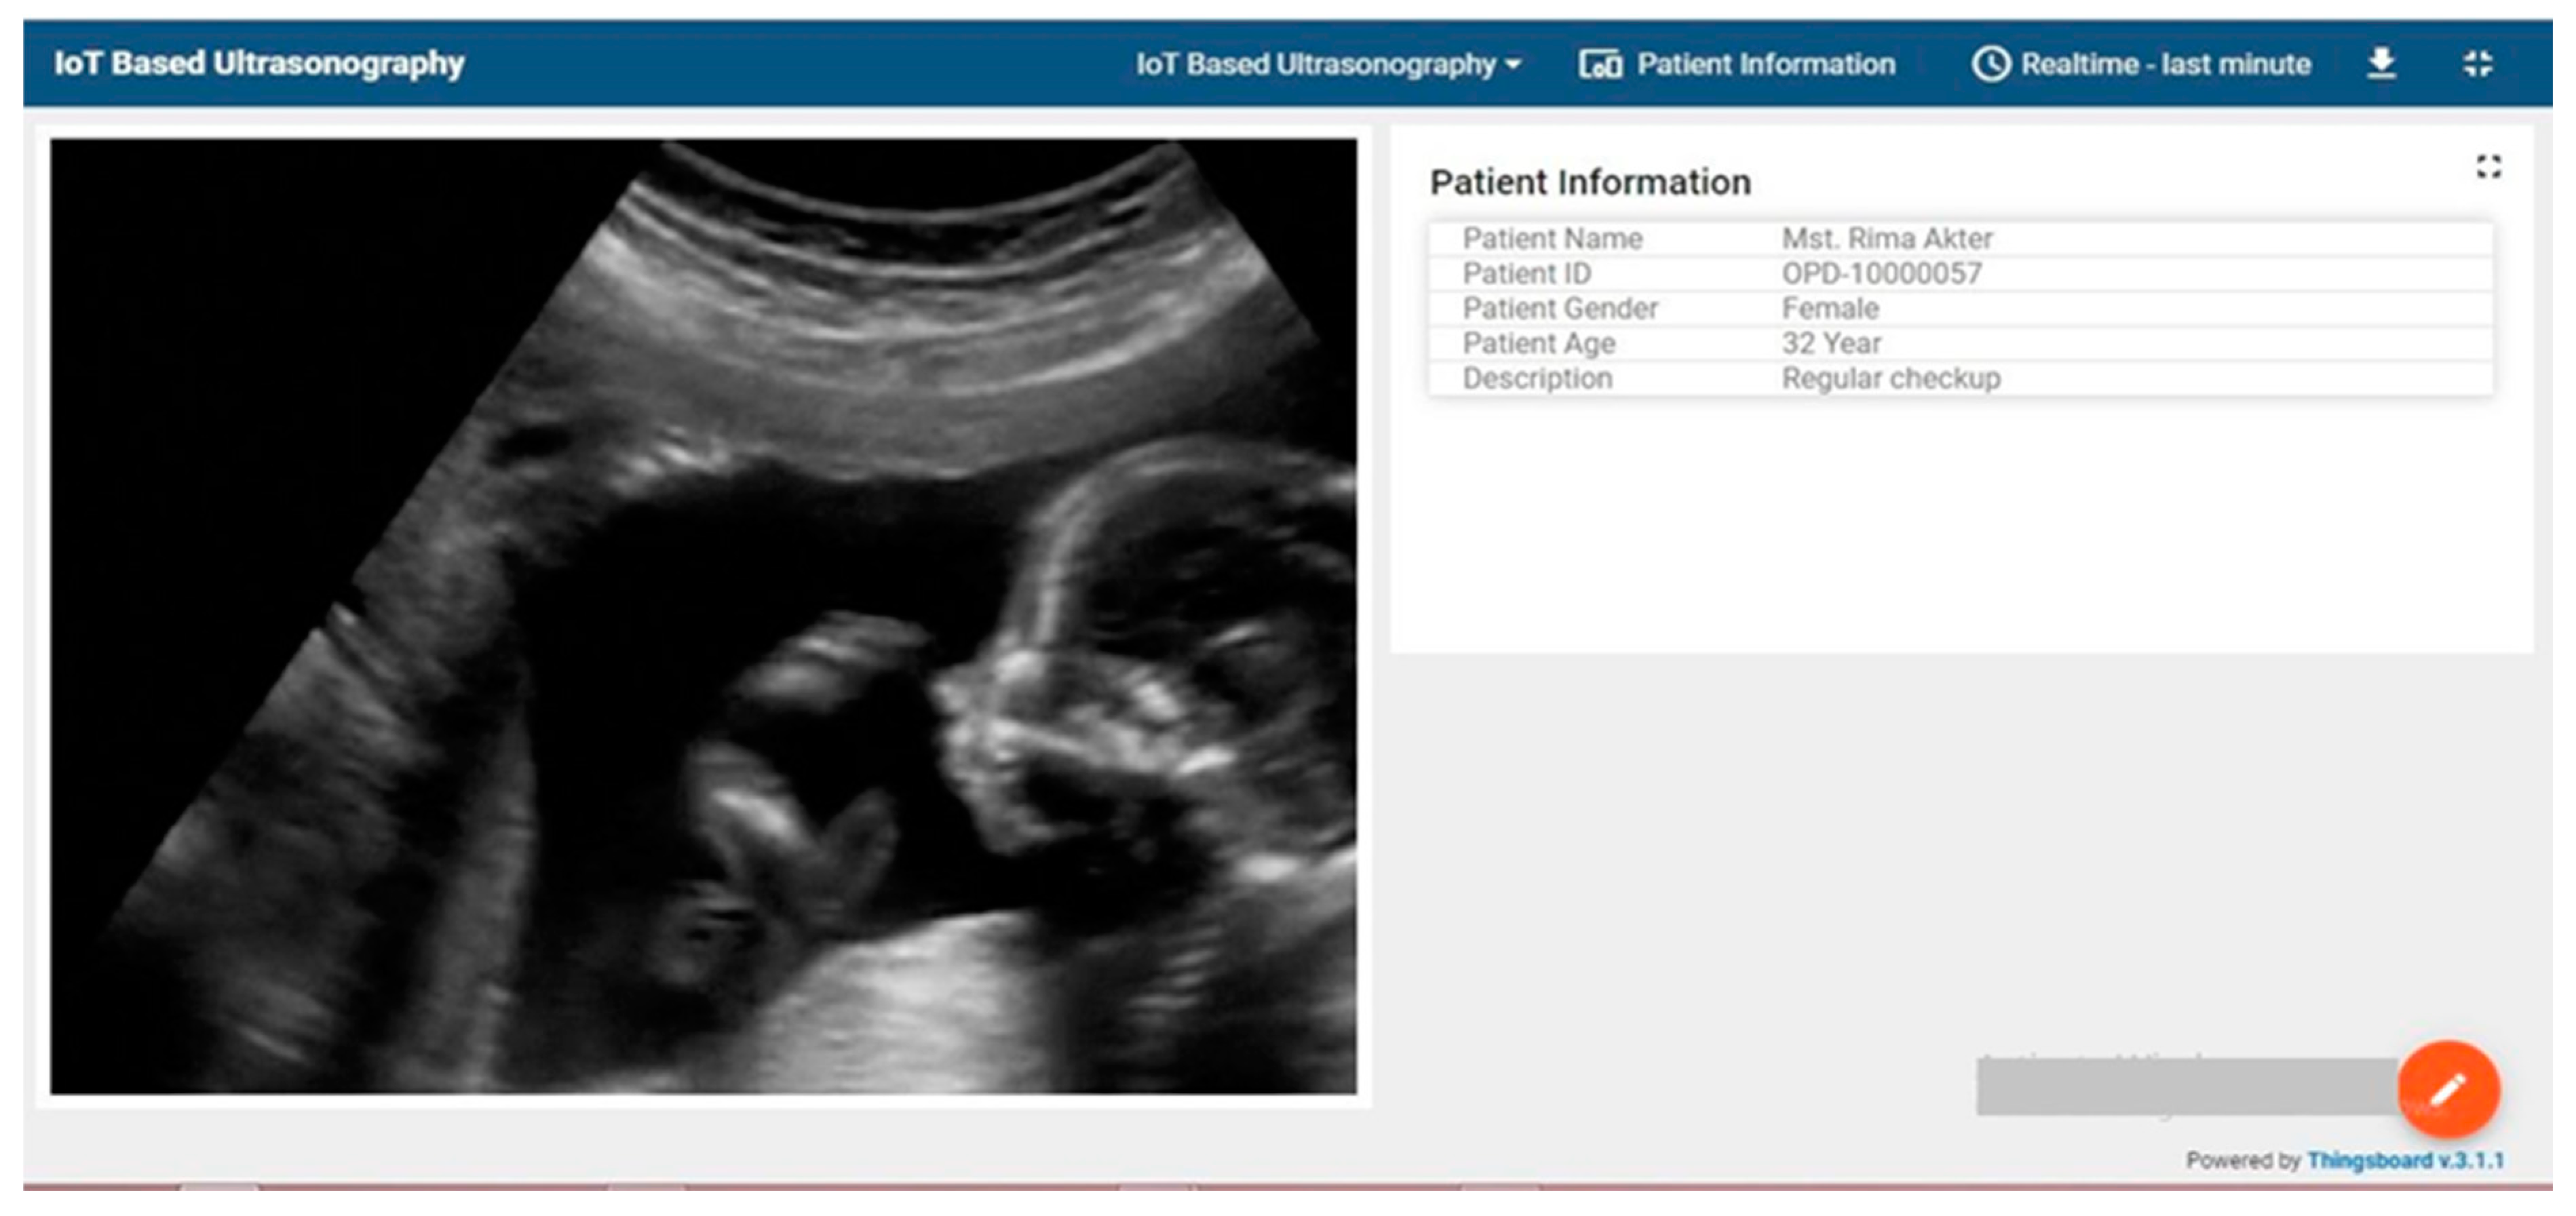

- Then, decrypt the image link and display it in the IoT server based on the client.

| (c) Custom Widget for image display | Source Code | Custom Modification | Makes sure to decrypt the generated encrypted link by using RSA private key to display patient image data |